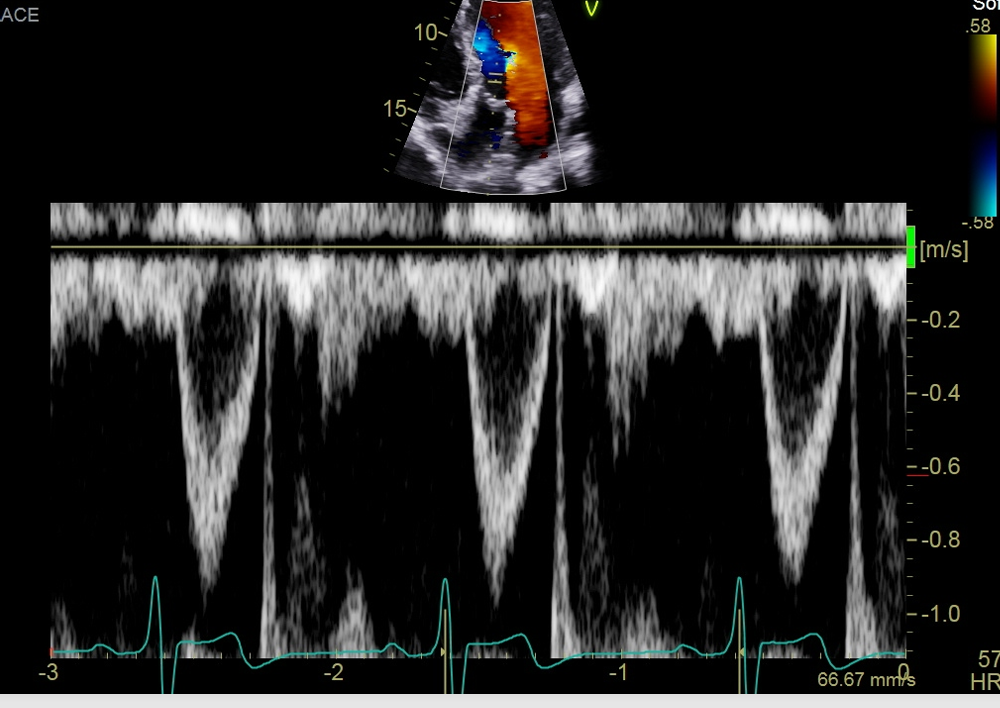

what single is this measurement for what are you going to peak, why would this doppler be important

this measure is for the pulmonary vein

Pulmonary vein peak systolic velocity (peak the S wave)

Peak D wave

peak the velocity of the atrial reversal or atrial duration

This will important when interrogate for MR, If the S wave is shorter than ourt D that is blunting so this coulf point to moderate or severe regurgitation if you see a reversal in these two